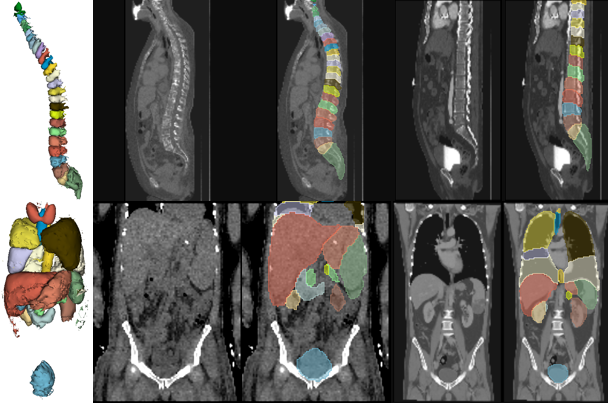

Visualization of Deformed Prior

Figure 5 shows the learned global priors and patient-specific deformed anatomy 𝐏𝐫^gsubscript^𝐏𝐫𝑔\widehat{\mathbf{Pr}}_{g}over^ start_ARG bold_Pr end_ARG start_POSTSUBSCRIPT italic_g end_POSTSUBSCRIPT learned by the TPS deform block as illustrated in Figure 2(b). The figure depicts that the learned global priors closely align with our understanding of generic anatomies of vertebrae and abdominal organs. Additionally, the prior anatomy is successfully deformed into different patient-specific anatomies. For instance, the spine anatomy in the left scan shows greater curvature, while the spine anatomy in the right scan appears straighter; the overall positions of the vertebrae also differ significantly.

Refer to caption

Figure 5: Visualizations of learned common priors (left) and their deformation to patient-specific anatomies (right).